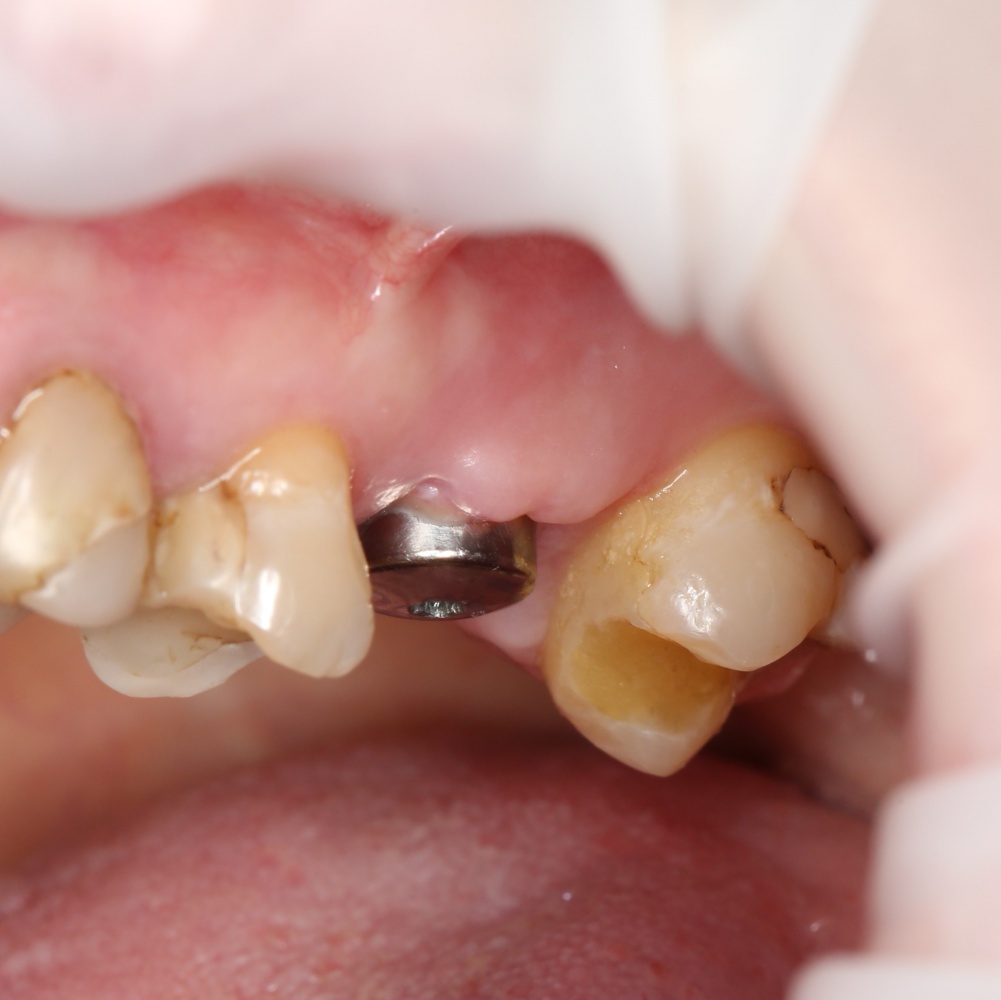

Простой синуслифтинг. Часть I.